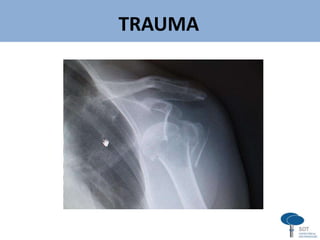

TRAUMA

Série Trauma de Ombro (Neer)

AP verdadeiro

(de Grashey)

Perfil escapular Axilar